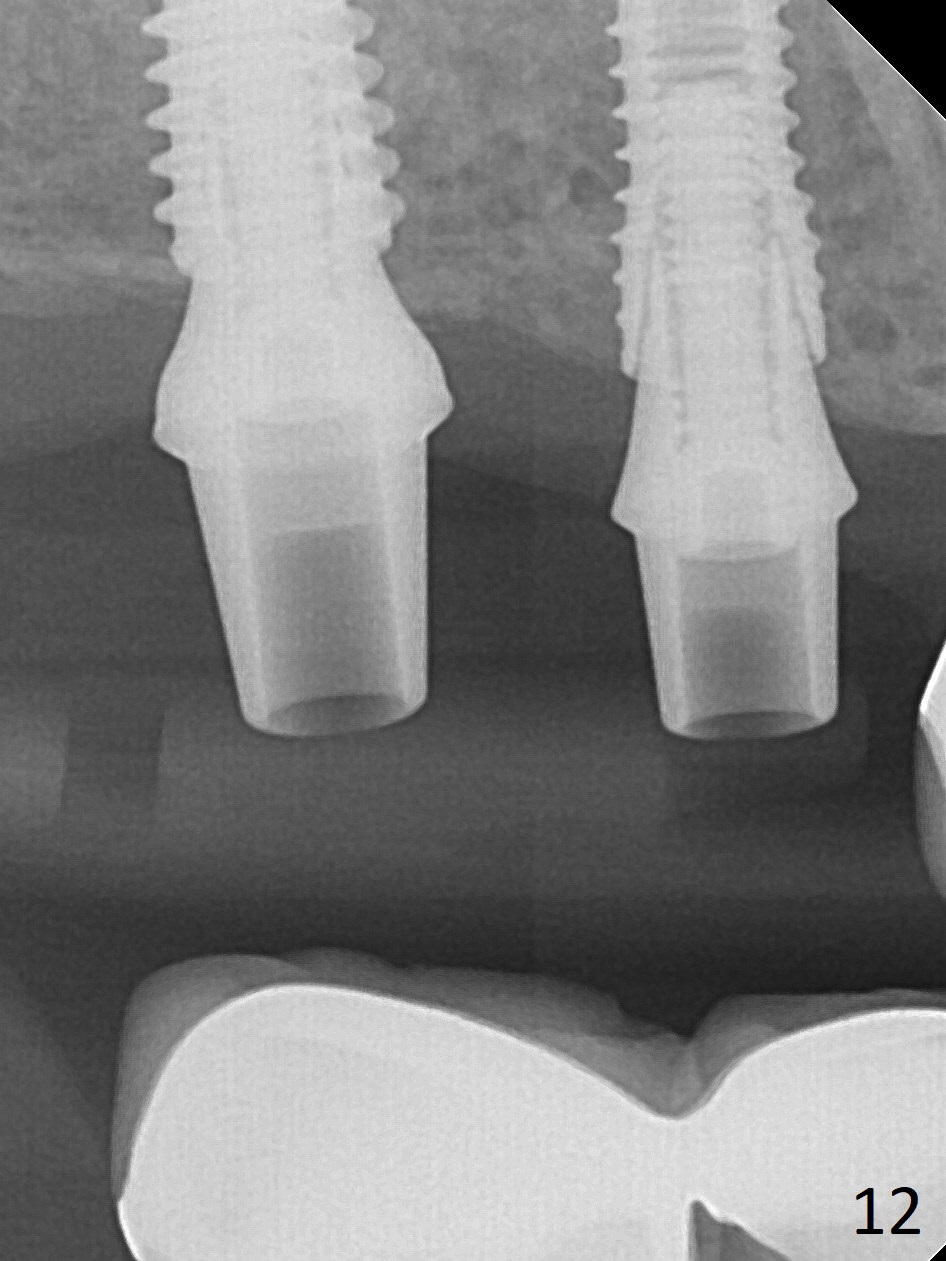

The ridge at #3,4 is wide (Fig.1). A surgical stent is placed (Fig.2) for initial osteotomy (Fig.3). When the stent is removed, the osteotomies need to move palatal (Fig.4 arrows). As two of 1.2 mm drills are in place (Fig.5), mesiodistal trajectories are found off (Fig.6). After the trajectories are corrected (Fig.7), the depth cannot be determined with PA (Fig.8, as compared to Pan (Fig.9)). Following 4.3 and 3.2 mm final drills at #3 and 4, 4.5x13 and 3.8x15 mm implants are placed with insertion torque of 35 and 50 Ncm, followed by 5.5x4(3) and 4.5x4(2) mm abutments (Fig.10). BWs show incomplete placement of the implant at #4 distal (Fig.11,12). Later the implant is placed ~ .5 mm deeper. Periodontal dressing is applied postop. CT-assisted surgical guide must be more efficient for this case with wide ridge. There is no bone loss around the implants 3 moths postop

(Fig.13).